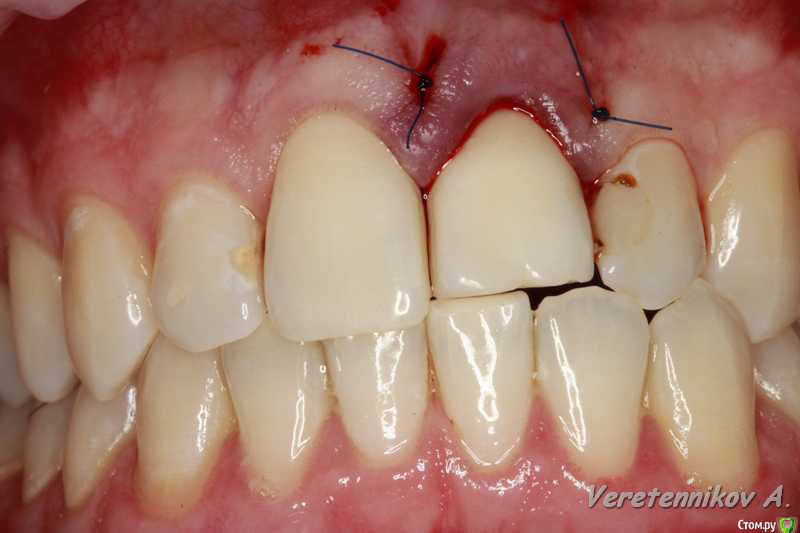

an_ver Опубликовано 15 декабря, 2015 Поделиться Опубликовано 15 декабря, 2015 Травма 21, немного сместился,удаление,имплантация SPI 4.2*13,ГенОсс+ ауто со сверла,для временной коронки использован свой зуб)),немного укоротили реж.край,чтоб не травмировать,унифлекс 5/0 18 Ссылка на комментарий